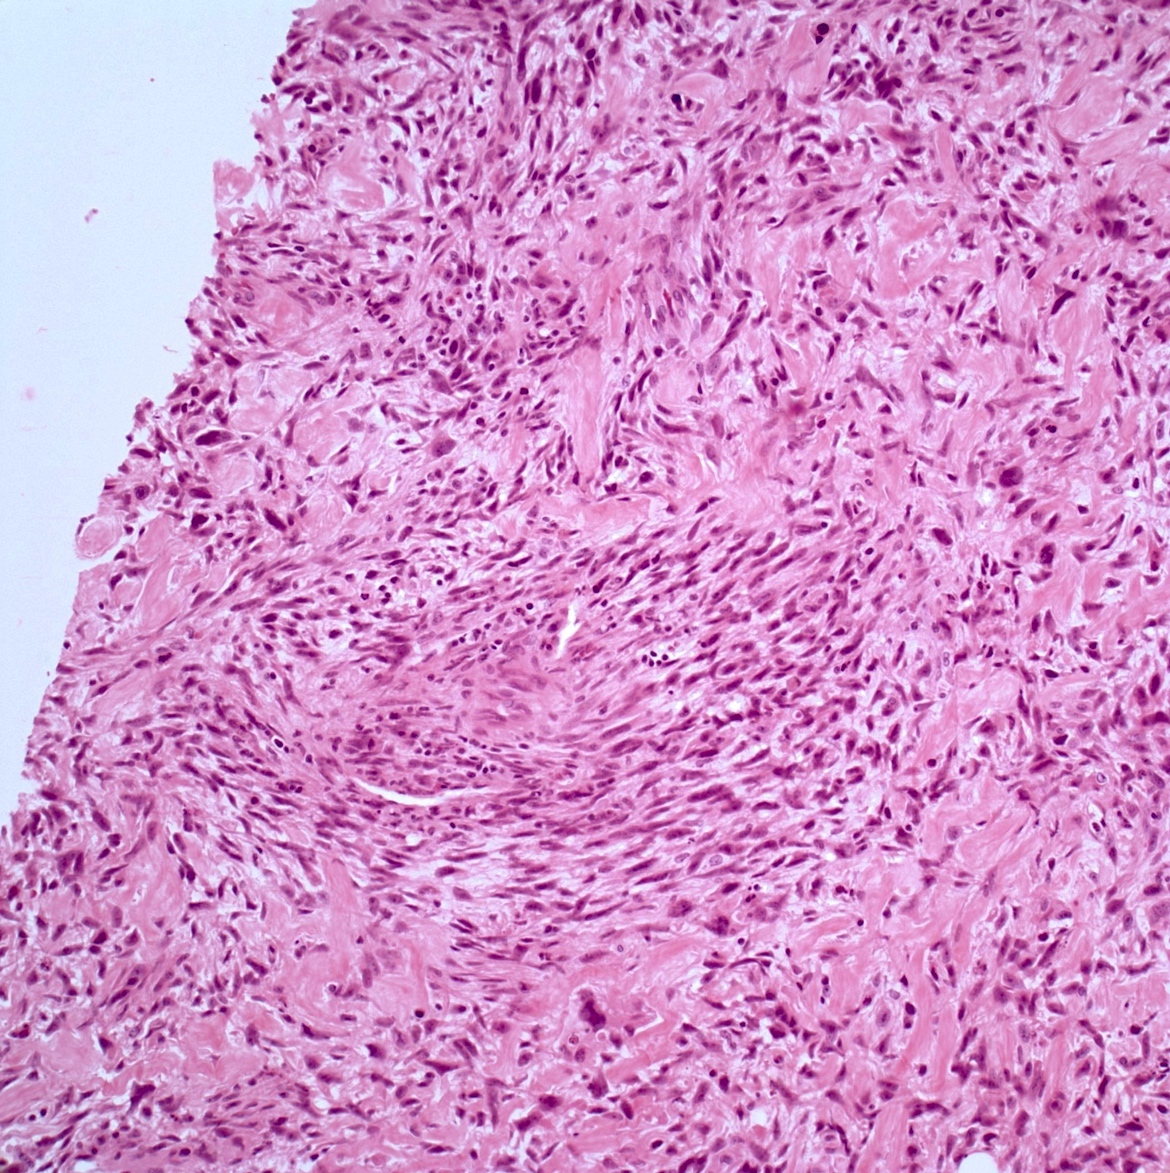

- Low grade central osteosarcoma:

- Permeative growth:

- Intramedullary (surrounds and erodes native trabeculae, fills Haversian systems)

- Cortical destruction and soft tissue invasion

- Neoplastic cells: fibroblast-like spindle cells (minimal atypia); hypocellular to moderately cellular

- Scattered mitoses may be seen

- Rare, scattered higher grade areas may be present

- Arranged in fascicles or interlacing bundles

- Neoplastic bone:

- Bone trabeculae (fibrous dysplasia-like): curved, branching or interanastomosing

- Longitudinal lamellar bone: like parosteal osteosarcoma

- Benign multinucleated giant cells: present in 33% of cases

- With or without scattered foci of atypical cartilage

Microscopic (histologic) images

Contributed by Jesse Hart, D.O., Borislav A. Alexiev, M.D. and AFIP

A 12 year old girl has a 10.5 cm intramedullary mass in the distal femur, which was resected (see gross and microscopic images). High power views demonstrate bland spindle cells. Which of the following is most accurate regarding this tumor?

A. Most likely, genetic abnormality is amplification of the MDM2 gene. The tumor is a low grade central osteosarcoma.